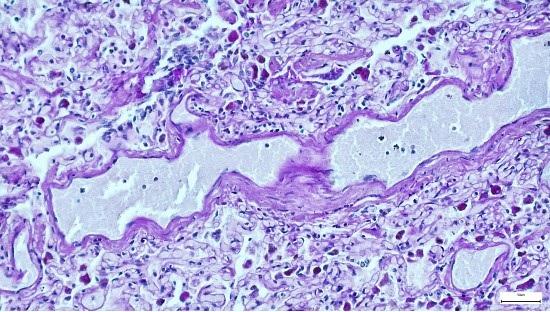

अमेरिकन नेशनल कैंसर इंस्टीट्यूट के मुताबिक, ‘किसी भी जीव की कोशिकाओं और ऊतकों की माइक्रोस्कोप द्वारा जांच किए जाने की प्रक्रिया को ही हिस्टोपैथोलॉजी स्टडी कहा जाता है’. इसमें हिस्टोलॉजी ऊतकों (tissues) की स्टडी है और पैथोलॉजी को बीमारी का कारण जानने से जोड़ा गया है.

किसी भी बायोप्सी रिपोर्ट की डिटेल में जांच के लिए इस तरह की रिपोर्ट का सहारा लिया जाता है, ताकि किसी व्यक्ति की बीमारी का पता लगाया जा सके. विस्तृत जांच के लिए जब ऊतकों को लैब में भेजा जाता है, तब उन्हें अलग-अलग करके माइक्रोस्कोप के जरिए उसकी जांच होती है.

मौजूदा वक्त में किसी भी पोस्टमॉर्टम रिपोर्ट को फाइनल करने में हिस्टोपैथोलॉजी स्टडी काफी जरूरी होती है. जिसे अलग-अलग चरणों में किया जाता है. जिसमें माइक्रोस्कॉप से टेस्टिंग के समेत सभी सेल्स की जांच की जाती है.